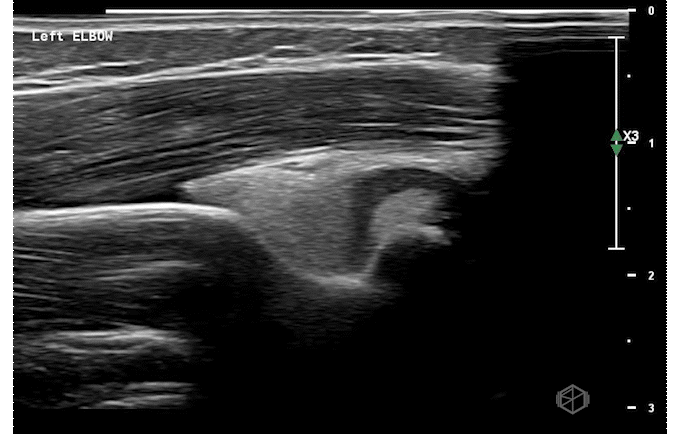

Our second SonoProp goes to Dr. Siri Tummala. Dr. Tummala scanned a 4-year-old male with LEFT elbow pain after injuring himself while going down a slide. Using the linear probe she obtained two views of the supracondylar area as seen below and compared it to the right elbow.

The LEFT elbow demonstrates an elevated fat pad with heterogeneous material within it representing lipohemarthrosis, while the right elbow demonstrates a normal posterior fat pad.

Diagnosis — Left elbow supracondylar fracture

• Ultrasound has high sensitivity (98-100%) and specificity (70-93%) for a supracondylar fractures (23142008, 26815896, 27277459). Lipohemarthrosis, a prominent dorsal fat pad are highly indicative of supracondylar fractures. Cortical disruption can be seen as well. When XR and US are both negative, the possibility of fracture can be rule out definitively (27697406).

• While it does not replace X-ray, ultrasound can be used when there is a high suspicion and the X-ray is equivocal or read as negative to diagnose occult supracondylar fractures.